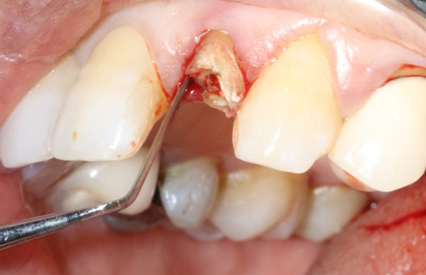

A 54-year-old female patient in good general health visited the outpatient department of the University Hospital Clinic of Odontology in Monastir, Tunisia, for therapeutic management of her left maxillary lateral incisor.Endo-buccal examination (Figure 1) revealed the presence of the 22 root

Figure 1. Occlusal view of the maxilla showing the fractured crown of the 22